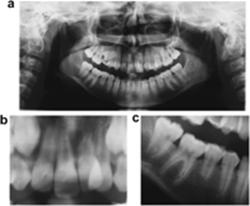

The following morphological characteristics and dental anomalies were seen in the subjects: invaginations in five (Figure 1), a narrow crown of the maxillary central or lateral incisors in one (not shown), abrupt root deflection of a maxillary incisor in one (Figure 3), slender or tapered roots in six (Figure 3), short roots in three (Figures 1 and 3), taurodontia in six (Figures 2 and 3), and agenesis in three (Figures 1 and 2). Pipette-shaped teeth were not registered.

View larger version:

Figure 3

(a) Follow-up radiograph of the permanent dentition in a girl aged 11 years 6 months. Abrupt root deflection of the left maxillary central incisor, slender roots of the mandibular first molars, short roots of the second premolars and mandibular incisors, and taurodontia of the second molars. A deviant resorption pattern of the right primary maxillary second molar is seen. Dental pantomogram (DPT; not shown) of the early mixed dentition showed unexpected early apical resorption of the primary teeth. (b) Enlargement of the DPT of the girl shown in (a). Abrupt root deflection of the left maxillary central incisor is seen in (c). Enlargement of the right mandibular region of the DPT showing taurodontia of the second molar, slender roots of the first molar, and a short root of the second premolar.